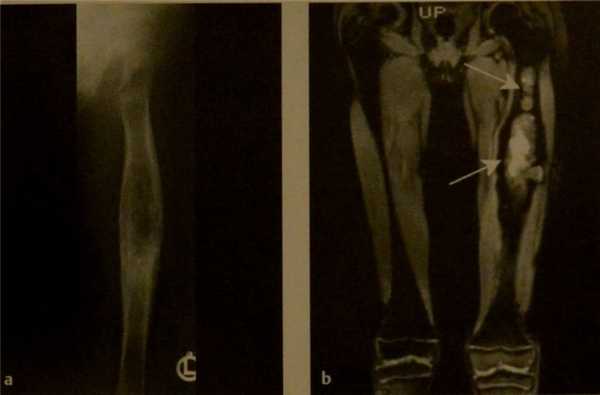

![Снимки МРТ и КТ. Остеосаркома у детей]()

Телеангиэктатическая остеосаркома левого бедра у девочки 8 лет. Рентгенография (а) и МРТ (b). Рентгенограмма выявляет преимущественно остеолитическое поражение кости. Изолированные остеосклеротические изменения визуализируются в нижней части опухоли. Коронарное изображение STIR (b) визуализирует всю распространенность опухоли (стрелки).